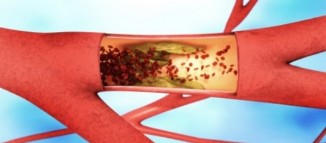

გაიწმინდეთ სისხლძარღვები და ათეროსკლეროზი არ შეგაწუხებთ! ნატურალური საშუალებებით მკურნალობა შინაურ პირობებში

ათეროსკლეროზი ჩნდება მაშინ, როცა არტერიების კედლები სქელდება, შედეგად კი დაზიანებული მიდამოებისთვის სისხლისა და ჟანგბადის მიწოდება რთულდება. კედლების..